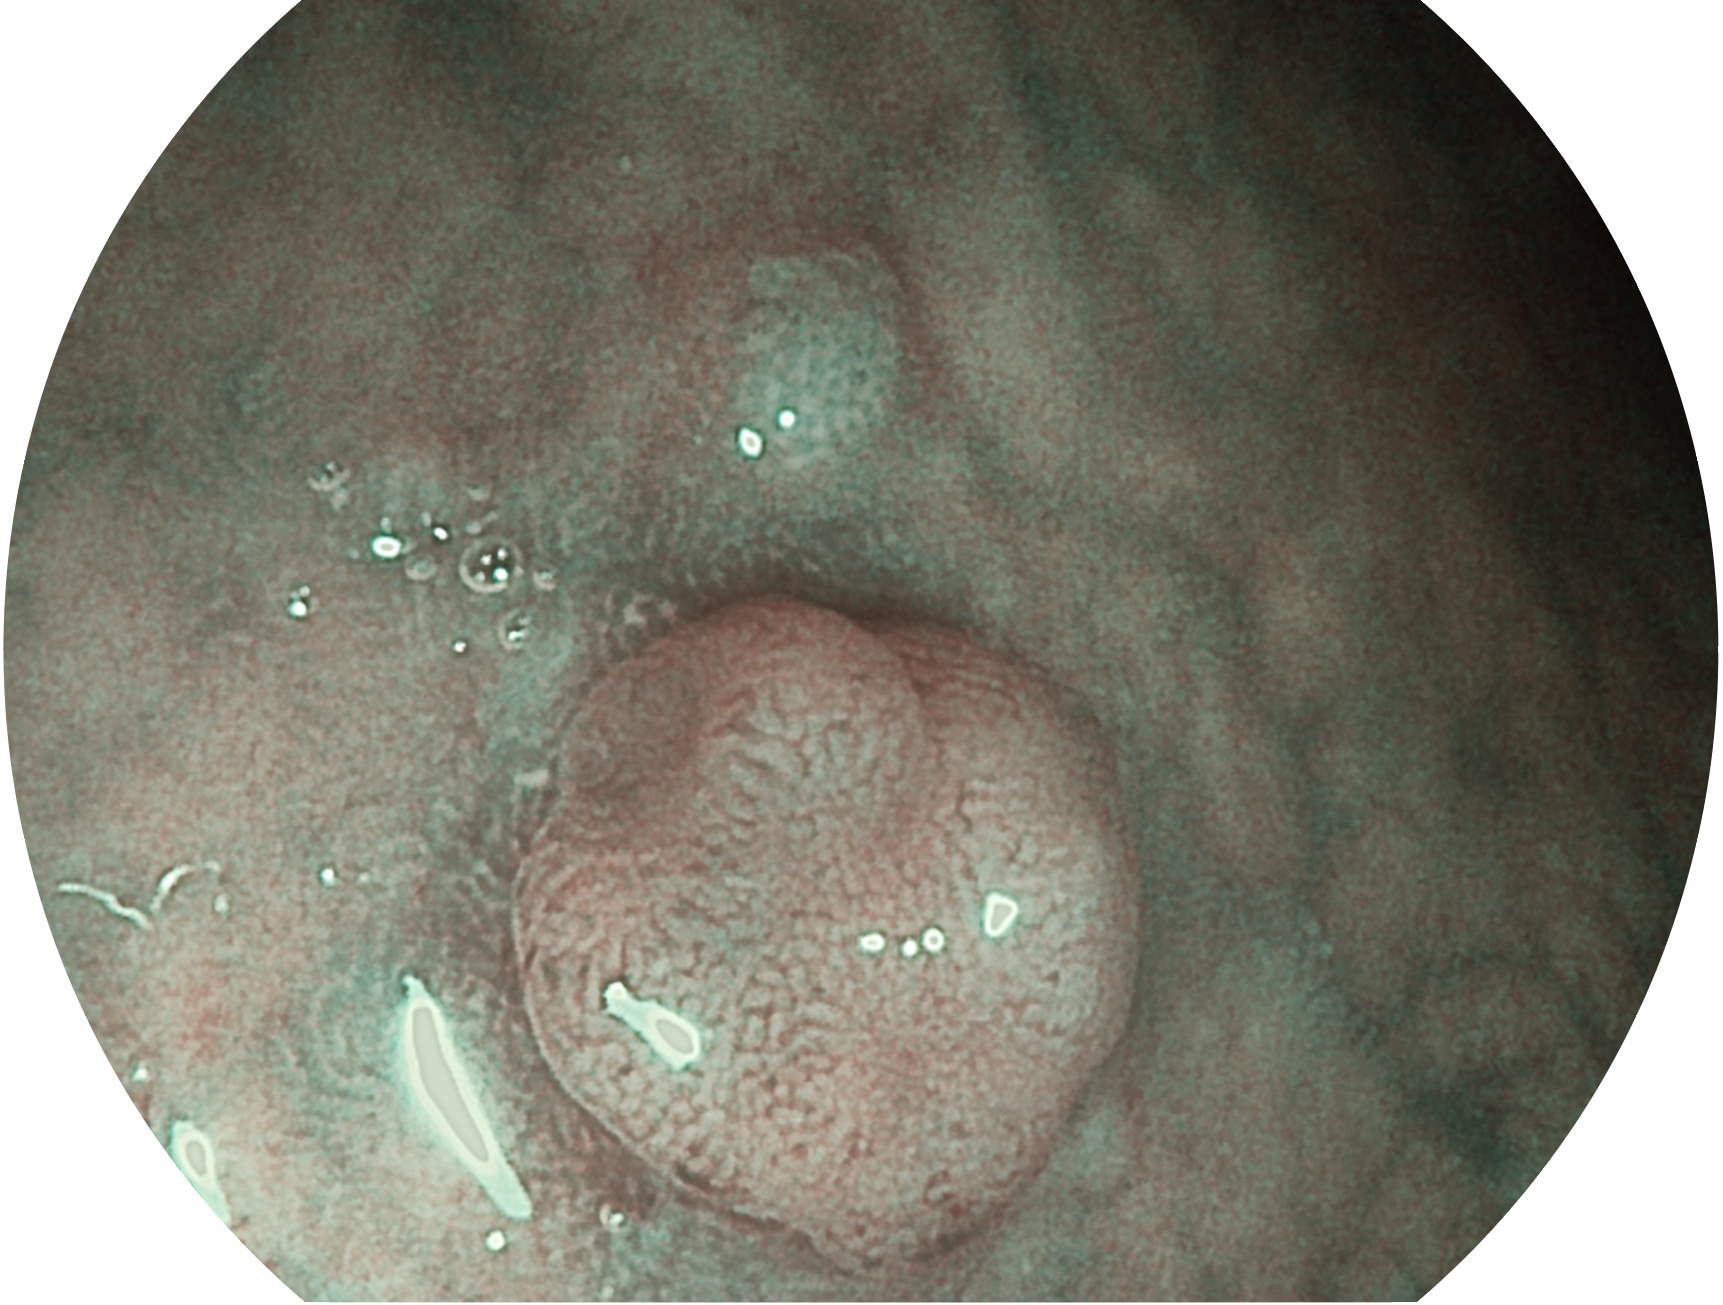

新葡的京集团8814检测站新开发的内镜染色技术,主要是基于多波长LED 光源的开发,VLS-55Q 四波长LED 光源是由四个不同颜色的LED光按照相应照明模式所规定的特定发光比例进行合束后形成,合束后形成的照明光的光谱由红光、绿光、蓝光及蓝紫光这四个不同的波段范围构成。具有更高光谱自由度,通过光谱比例的控制,实现了聚谱成像技术,英文全称为“Spectral Focused Imaging, SFI”,缩写为“SFI”和光电复合染色成像技术,英文全称为“Versatile Intelligent Staining Technology, VIST”,缩写为“VIST”。